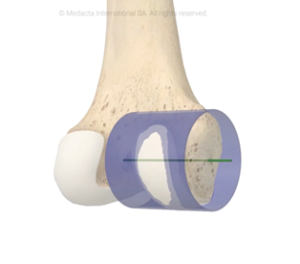

The tibial component consists of two parts:

Tibial baseplate: A metal platform fixed to the top of your shin bone (tibia) using either bone cement or a press-fit technique.

Tibial insert: A high-grade plastic spacer (made of ultra-high-molecular-weight polyethylene) that sits atop the baseplate.

This plastic insert functions like your knee’s natural cartilage. It cushions the joint, absorbs shock, and allows the femoral component to glide smoothly over the tibial surface. Modern inserts are engineered to be wear-resistant and may include antioxidant-enhanced materials such as Vitamin E to improve durability. In some cases, if only the plastic insert wears out over time, it can be replaced without disturbing the metal implants.

Fixed bearing designs have a polyethylene insert locked into the tibial baseplate. This is the most commonly used type and is suitable for many patients.

Mobile bearing designs allow some movement between the insert and the baseplate, which may offer better rotation for selected patients.